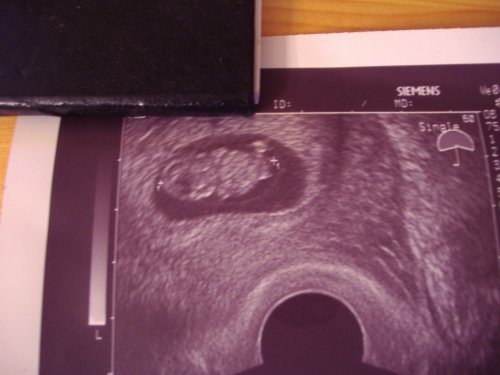

Ok: 37. héten született rossz áramlás miatt (Ákos is, csak ő a 38. héten), + 2320g volt (kicsi, 2-3 héttel elmaradt az átlagtól), + mivel nálam odabent valami gyulladásnak indult (ezért ki is takarított a doki) napi 2 adag antibiotikumot kapott napokon keresztül